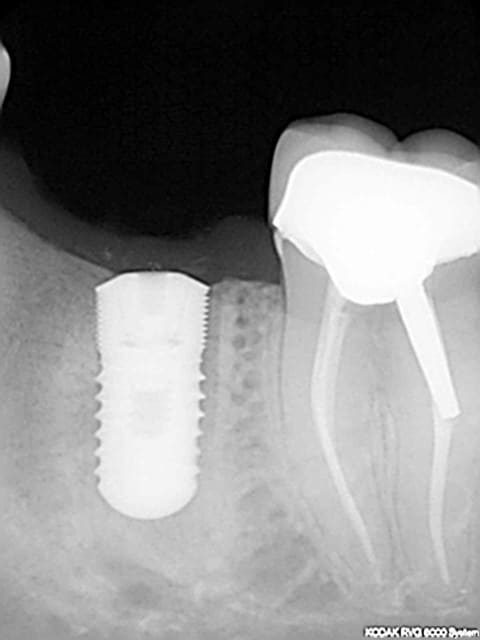

perte de 36 mise en place d'un euroteknika 4.8*10 parce qu'image apicale à 13 donc pas envie de mettre un 12

a posteriori oui mais espace plutôt limite 11.5mm entre 35 et 37 même en 3.3 c'était pas terrible au niveau distance implant implant et dent implant c'est pour ça que j'ai opté pour plus gros diamètre